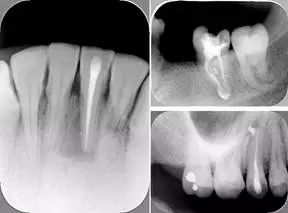

三、开髓孔

1. 正常开髓孔的位置和大小

左图为正常开髓孔的大小和位置。左边图为下颚,右边图为上颚。

2. 根管治疗中开髓孔的设计标准

根管治疗需去除髓腔内容物(去除髓室顶),建立所有根管的入路,允许冲洗液大量冲洗。开髓孔的设计标准以建立通路为目的,从而建立良好的视野和术野。

( 1 )直线通路:根管治疗时需要一个直线通路,直线通路能够达到根尖三分之一

测量标准:以允许根管器械直线并直接进入根尖 1/3 且不接触冠方各壁为标准。

( 2 )髓腔其他改变:如髓室顶、继发性牙本质、修复性或增龄性牙本质。见左图。

右图中有继发性牙本质,切削后获得直线通路。